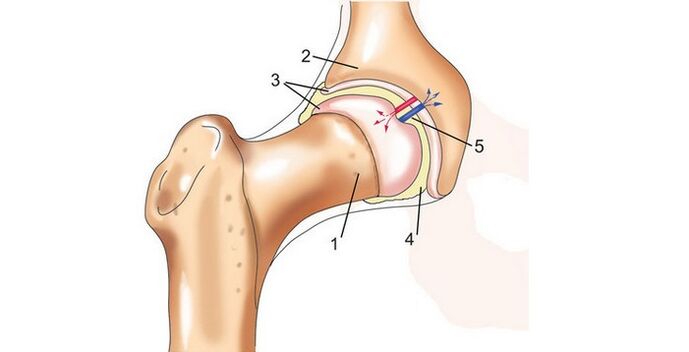

Das Hüftgelenk liegt zwischen Darmbein und Oberschenkelknochen. Aus diesem Grund werden Entzündungen und Pathologien als Arthrose des Hüftgelenks der Iliosakralgelenke bezeichnet.

Der Raum zwischen ihnen umfasst auch die Synovialmembran und den hyaliner Knorpel; Zusammen sorgen alle diese Komponenten für die normale Funktion des Gelenks. All dies ist auf dem Foto einer Arthrose des Hüftgelenks deutlich zu erkennen.

Die Arbeit des hyaliner Knorpels ähnelt der eines Schwammes. Beim Zusammenziehen gibt es je nach Belastung des Gelenks die nötige Menge an Flüssigkeit ab, die eine schmierende Wirkung hat. Sobald die Belastung aufhört, füllen sich die Knorpelporen wieder mit Flüssigkeit. Einer der Gründe für die Entstehung einer Erkrankung wie der Hüftarthrose ist eine Veränderung der Eigenschaften der Gelenkflüssigkeit.